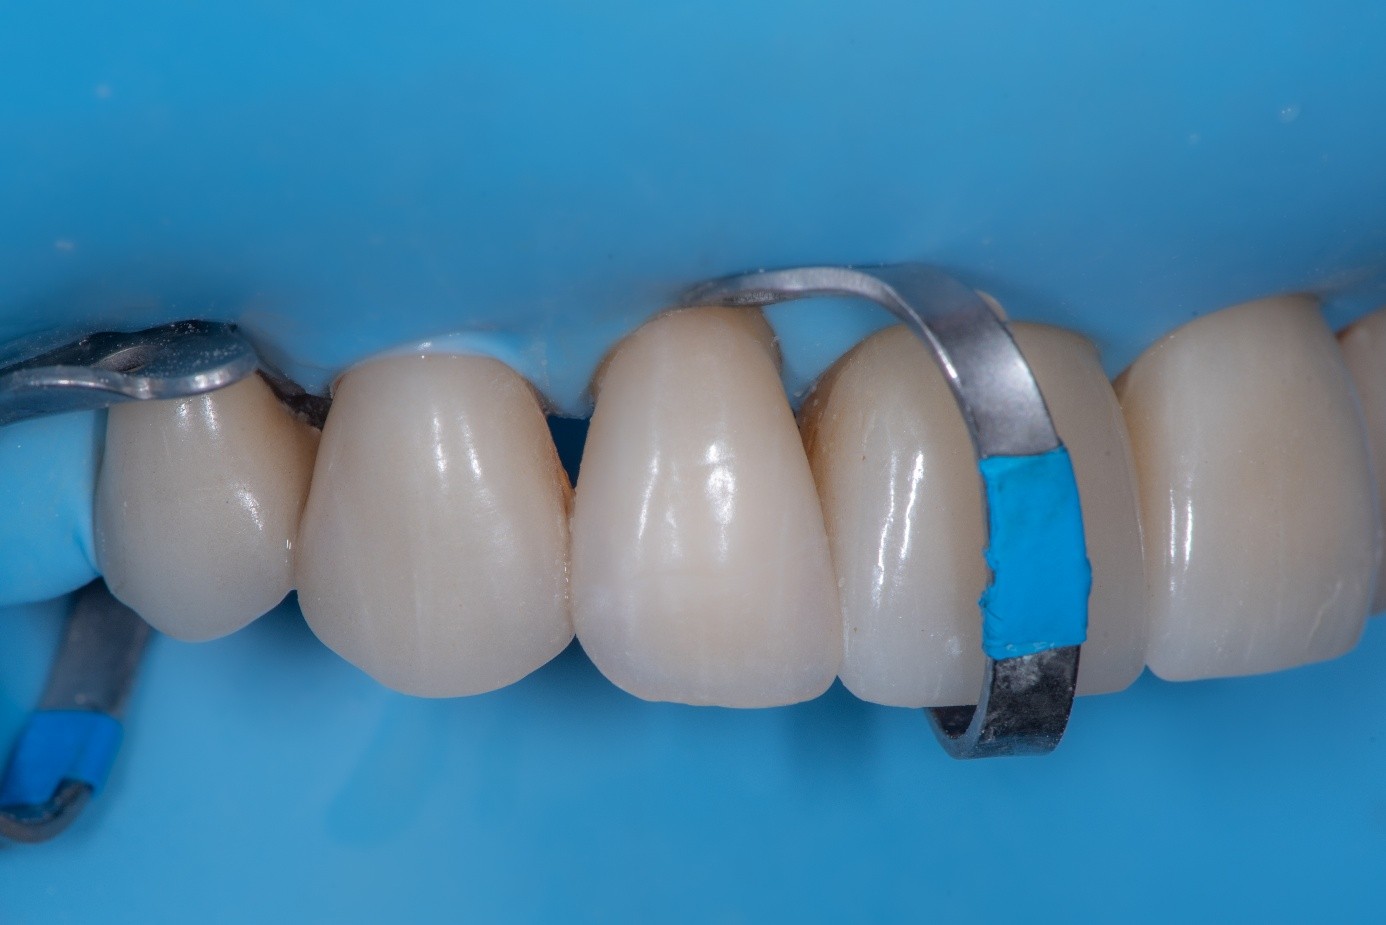

Intraorally, absolute rubber dam isolation was achieved to ensure a contamination-free environment (Figure 30). The prepared tooth was air-abraded with aluminum oxide to clean the surface and increase surface energy. A primer and bonding agent were applied to the tooth surface.

(30.) Intraoral view after absolute isolation with a rubber dam, showing the prepared tooth surface cleaned and roughened with sandblasting, ready for adhesive application and bonding to the crown.

Figure 30